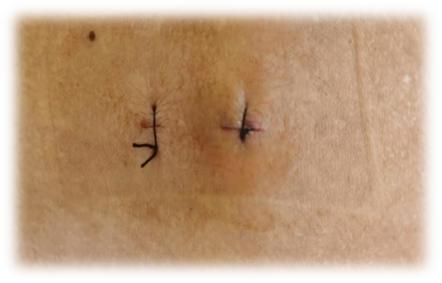

患者男性,57岁,因“腰部伴右下肢急性疼痛,加重10小时”入院,诊断:腰椎管狭窄症,腰椎间盘脱出。患者不能下床行走,卧床休息不能缓解,遂收入院治疗。为迅速缓解患者症状,综合患者病情,林雪林主任带领团队经过周密术前讨论和规划,决定采用全麻下UBE技术椎管减压、神经松解、椎间盘髓核摘除手术。手术视野清晰,操作灵活,手术过程安全、微创、高效,术后仅留下2个单孔小切口,患者疼痛、麻木症状得到有效缓解,术后第1天即可下地行走,恢复良好,顺利出院。患者出院后随访疗效满意。本次UBE技术的成功开展,标志着我院脊柱外科在微创内镜领域取得了进一步拓展升级。